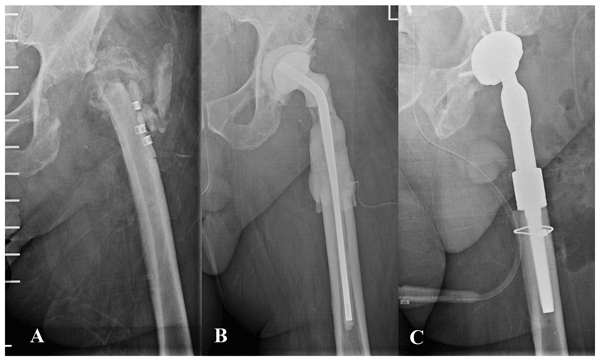

Short summary

This is a meta-analysis of six studies describing the cutoff values of white blood cell count and polymorphonuclear percentage in synovial fluid for the diagnosis of acute postoperative peri-prosthetic joint infection (PJI).

We found that both the WBC count and PMN percentage are good markers for diagnosis of acute postoperative PJI. However, the synovial WBC count is more powerful in diagnosing acute postoperative PJI.